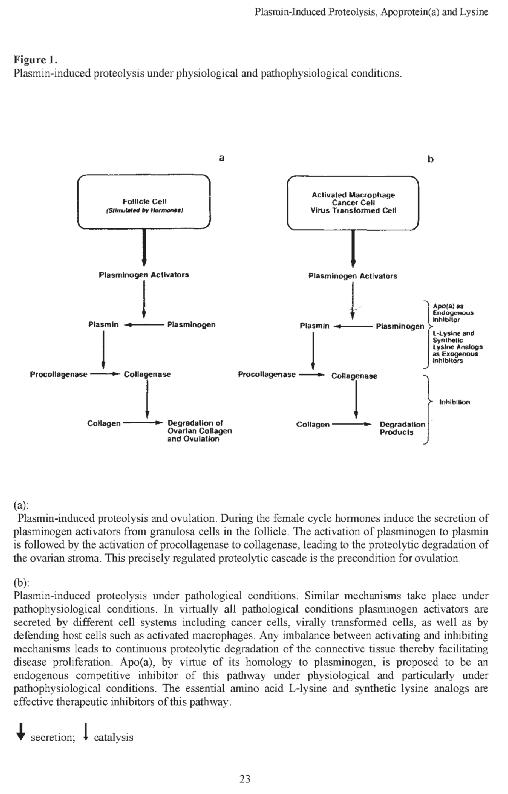

Le scoperte riportate nel seguente capitolo sono state fatte più di due decenni fa. La pagina a fianco mostra una pagina del mio manoscritto, pubblicato all'inizio del 1992 con il titolo "Proteolisi indotta da plasmina". Descrive per la prima volta che il meccanismo chiave della diffusione del cancro, la digestione del collagene, può essere bloccato da sostanze naturali. Il premio Nobel Linus Pauling ha sostenuto la vasta portata delle conclusioni di questa pubblicazione: l'attuazione di queste scoperte nella medicina porterà al controllo naturale del cancro. Immediatamente dopo questa pubblicazione, la digestione del collagene ha assunto un ruolo centrale in molte conferenze scientifiche. Ha inoltre innescato una corsa tra le aziende farmaceutiche per poter trovare delle molecole di origine sintetica, capaci di bloccare questo meccanismo, che le industrie potevano brevettare. Dieci anni dopo, il 12 maggio 2002, il San Francisco Chronicle ha pubblicato un articolo su questa intensa gara intitolato Misdiagnosis (Errori di diagnosi). Senza fare riferimento al rapporto originale sugli esiti di questi studi, riportava la gara tra le aziende farmaceutiche per trovare quello che il giornale chiamava il ‘Santo Graal della medicina’, la soluzione per la battaglia contro il cancro.

Plasmin-Induced Proteolysis and the Role of Apoprotein(a), Lysine, and Synthetic Lysine Analogs

Matthias Rath e Linus Pauling Journal of Orthomolecular Medicine, 1992, 7, 17-22

il testo integrale è contenuto in appendice